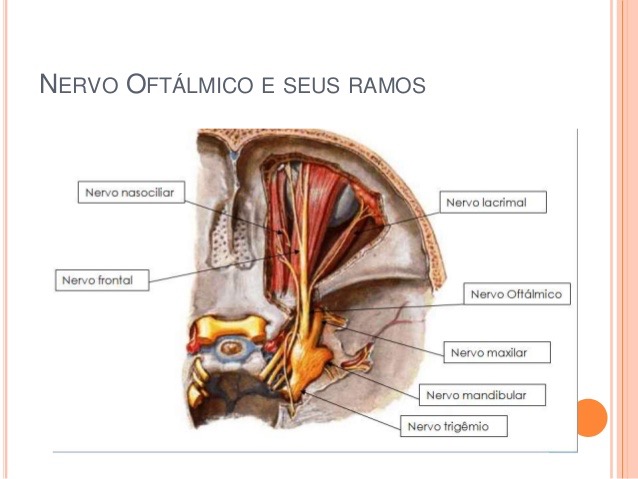

Nervo oftálmico V 1

Sai do gânglio do trigémio e dirige-se superiormente para atravessar a fissura orbital superior.

Dá as seguintes ramas:

Nervo Frontal

Nervo lacrimal

Nervo nasociliar

Este nervos, todos sensitivos são responsáveis pela informação do tipo tacto, dor, temperatura e informação proprioceptiva da conjuntiva, córnea, olho, órbita, testa, etmoide e seios frontais.

O nervo lacrimal leva informação sensitiva da glândula lacrimal, mas não é responsável pela sua secreção (provém do parassimpático do VII).

O nervo nasociliar inerva toda a mucosa da cavidade nasal e dos seios aéreos etmoidais.

O principal local onde este nervo pode ser perturbado é a nivel da fissura orbital superior, ou seja entre a ala maior e menor do esfenoide.

Quando existe uma perturbação a este nivel além das dores no território cutáneo de V1, podemos ter alterações lacrimais, de iridodilatação (pela relação com o gânglio ciliar), e dores no olho (bastante comum em consulta).

Por isso, sempre que suspeitarmos de uma lesão a este nivel, devemos rever os ossos em relação com o esfenoide nesta zona, nomeadamente o frontal, etmoide, maxilar superior, unguis e temporal, sem nos esquecermos do anel de zinn.